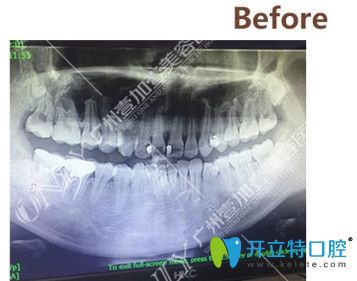

▼矯正前拍攝的CT

矯正前拍攝的CT

拍了CT之后,醫(yī)生根據(jù)我的情況給我進(jìn)行了分析,我的情況還不算特別復(fù)雜,牙套可以選擇金屬的、半隱形的以及隱形的,問清楚了這幾種牙套的區(qū)別和價格之后,我選擇了價格中等,美觀度稍高的半隱形陶瓷牙套。